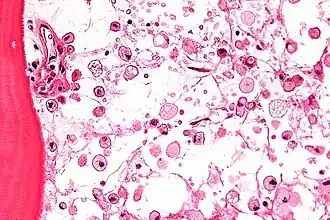

Las células que acumulan el glucocerebrósido son denominadas células de Gaucher, y adquieren un aspecto característico:[6] se muestran grandes, con aspecto mesenquimatoso, núcleo no desplazado y citoplasma con aspecto de "celofán arrugado". Las podemos ver sobre todo en médula ósea, hígado, bazo y ganglios linfáticos.[6]

Las técnicas principales para su diagnóstico son el ensayo fluorométrico de la actividad de la enzima responsable, la búsqueda de macrófagos que tienen el citoplasma con aspecto de "celofán arrugado" y el núcleo excéntrico en la médula ósea conocidas como "células Gaucher". También se realizan estudios genéticos, pero estos son menos comunes, pues se han identificado 200 mutaciones diferentes del gen que codifica la glucocerebrosidasa. Este se basa en el estudio de 4 mutaciones comunes y otras 7 menos frecuentes.